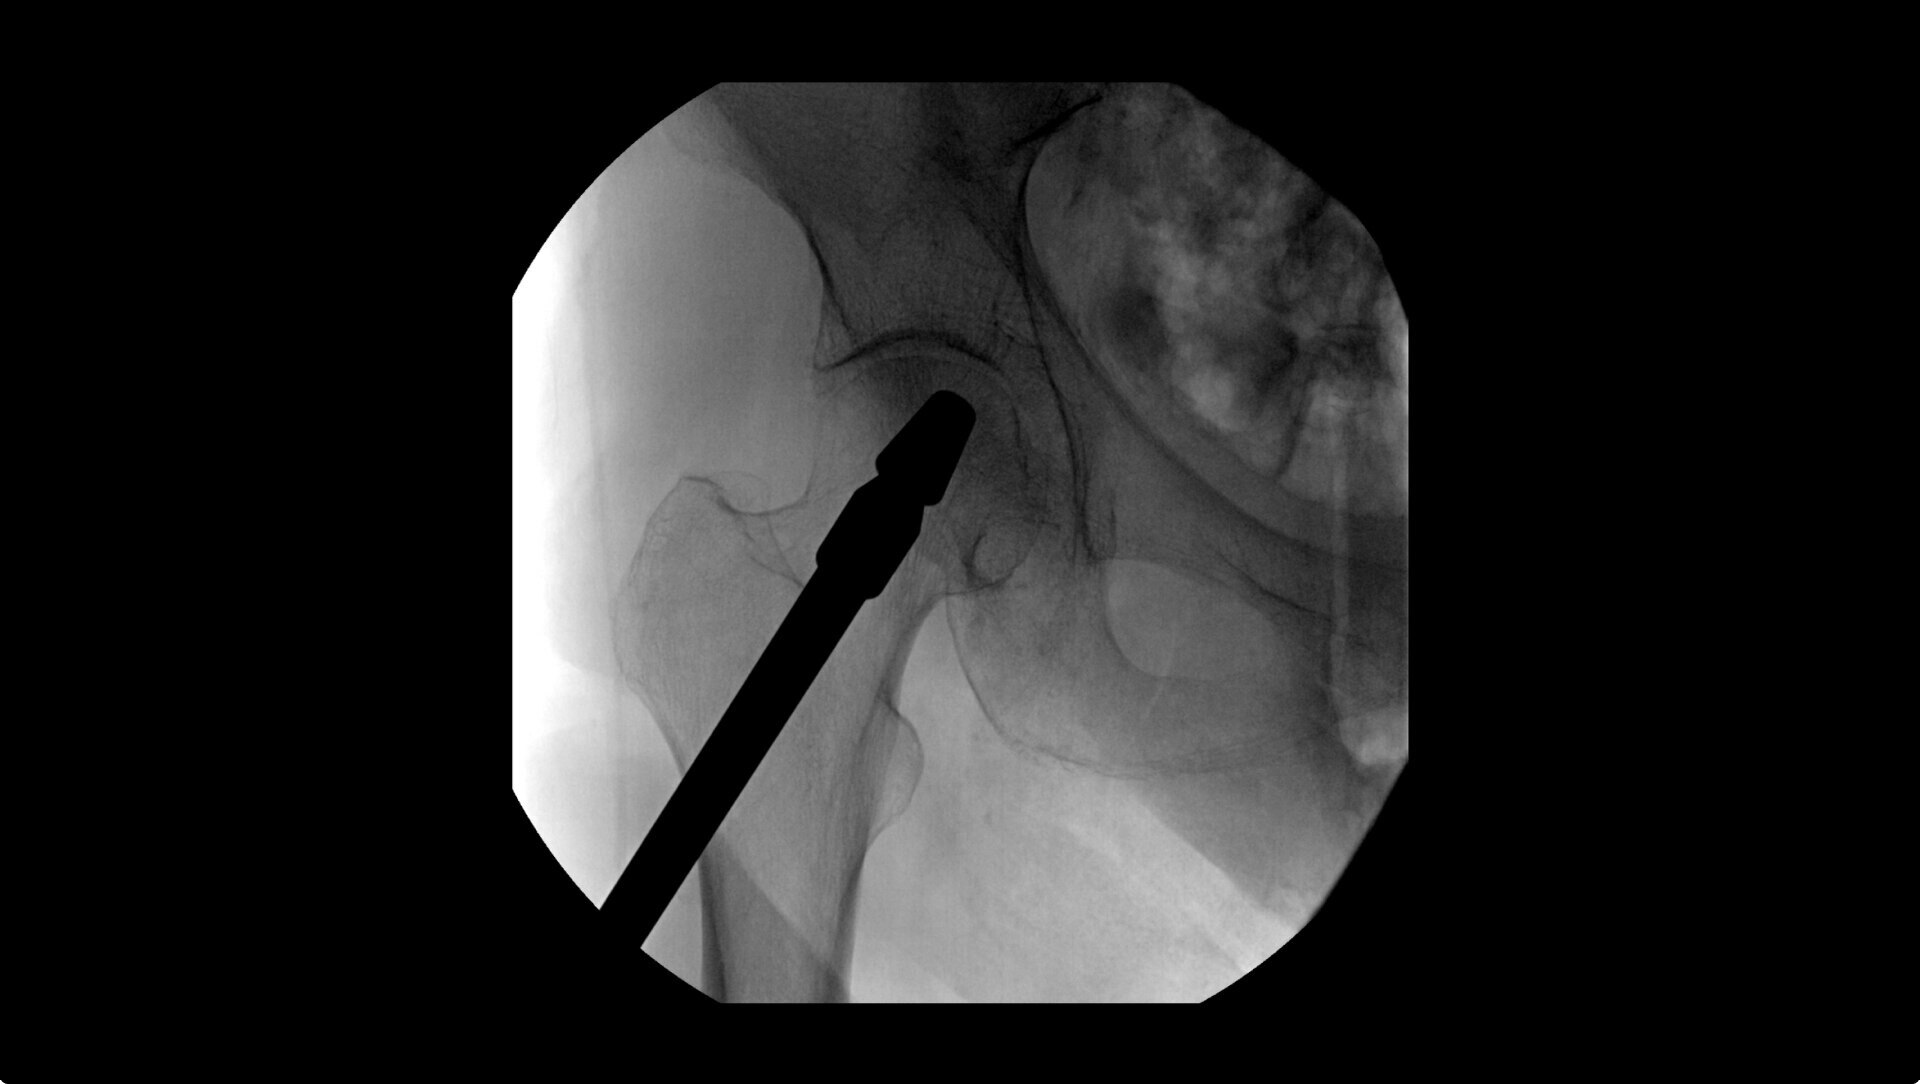

OEC C-arms provide orthopedic imaging with a large field of view optimized to clearly visualize orthopedic anatomy, such as the entire long bone femur or minute fractures in extremities. A clear display with comfortable viewing can easily show AP and lateral views, enabling efficient procedure planning.

During hip or femur imaging, capture up to 22% more Field of View by positioning detector closer to patient anatomy with the OEC low-profile X-ray tube housing compared to mono-block C-arms.

Complex orthopedic procedures require powerful imaging systems. OEC premium C-arms perform in a variety of procedures such as:

• Hip fracture fixation

• Hip replacement